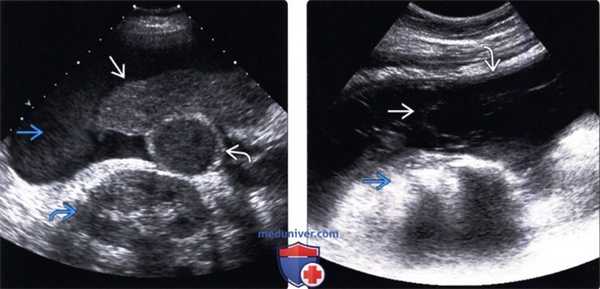

(Левый) На поперечном УЗ срезе в правом верхнем квадранте живота определяется цирротическая печень малых размеров. Определяется геморрагический асцит, что должно вызывать подозрения о наличии кровоточащего узла печеночноклеточного рака. Желчный пузырь заполнен ела джем, его стенки утолщены. Также обратите внимание на эхогенную правую почку.

(Правый) Пациент с сепсисом и болями в животе. Поперечный УЗ срез правого фланка среднего отдела живота. Осумкованный асцит , определяются перегородки и смещение кишечника. Выполнен парацентез, диагностирован перитонит, вызванный Pseudomonas и развившийся вследствие перфорации кишки.